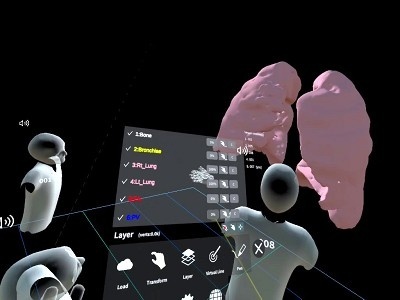

今回の授業ではこの1年間に習った内臓や筋、血管や神経といった臓器がどのように体内に存在し、その内部構造がどうなっているのかを、VR(3次元の仮想空間)で理解していきます。

これまでの授業では、教科書の2次元での説明が主であり、体の中を見ることが出来ない為、なかなか内部構造を理解するのが困難なようでした。

しかし、このVRを用いた授業では、「へえ~」「なるほど」と仮想空間にある臓器を持ったり、位置の確認をしたり、のぞき込んだりと楽しく授業を受けていました

- 肺